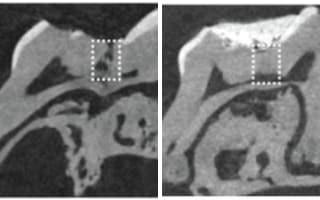

研究人员在小老鼠的牙齿钻孔后填满海绵,海绵浸泡过三种类型的糖原合成酶激酶-3抑制剂 (GSK-3)其中一种,这其中之一种抑制剂叫“Tideglusib”,已经测试过可以用来治疗阿兹海默症,GSK-3抑制剂被认为可以降低大脑中β类澱粉蛋白质和Tau蛋白的数量。

填入海绵六个星期之后,研究人员检查了小老鼠的牙齿,海绵都消失了,在那个地方是全新的、健康的牙本质,他们星期一在《科学报告》(Scientific Reports)中发表了他们的研究工作。